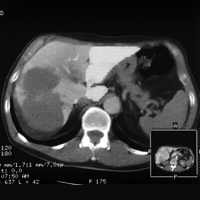

Virtual hepatic resection using three-dimensional reconstruction of helical computed tomography angioportograms (2001)

Wigmore, Stephen J and Redhead, Doris N and Yan, Xue J and Casey, John and Madhavan, Krishnakumar and Dejong, Cornelis HC and Currie, Elspeth J and Garden, O James

Annals of surgery, vol. 233 (2): 221–226